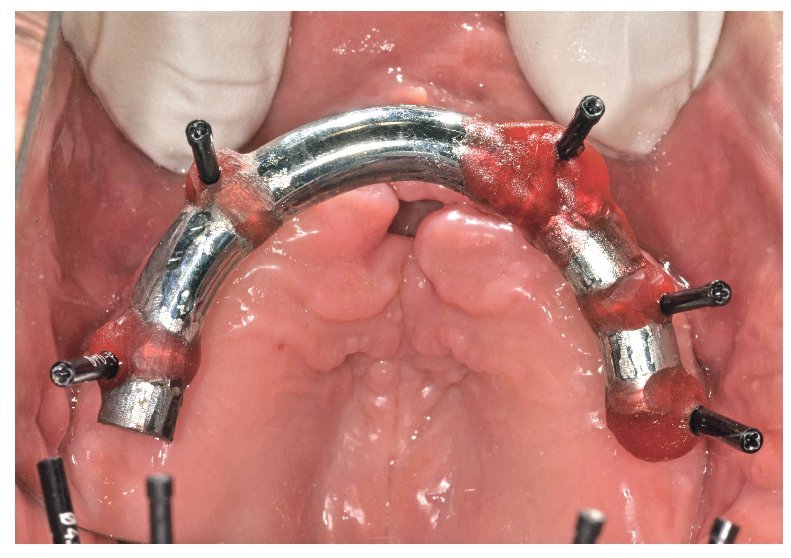

La confección de los modelos maestros requiere gran meticulosidad en el procedimiento y en la elección de materiales, dado que debe estar garantizada una fidelidad dimensional óptima. Con todo, no existe la certeza absoluta de que los modelos maestros reproduzcan adecuadamente la situación intraoral. Esto se comprueba mediante la confección de cuerpos de ensayo colados (fig. 80), los cuales se fijan sobre los pilares. Se trata de elementos de ensayo y control (figs. 81 y 82) para la introducción de la siguiente fase, durante la cual se confeccionan las estructuras fresadas. De este modo se evita el peligro de tener que repetir la confección o de puntos de soldadura tras las correcciones.

Fig. 80. Los modelos maestros de los maxilares superior e inferior con plantillas de comprobación para conciliar la posición del implante.

Fig. 81. El control clínico de la plantilla de comprobación del maxilar superior en la cavidad oral.

Fig. 82. El control clínico de la plantilla de comprobación del maxilar inferior en la cavidad oral.